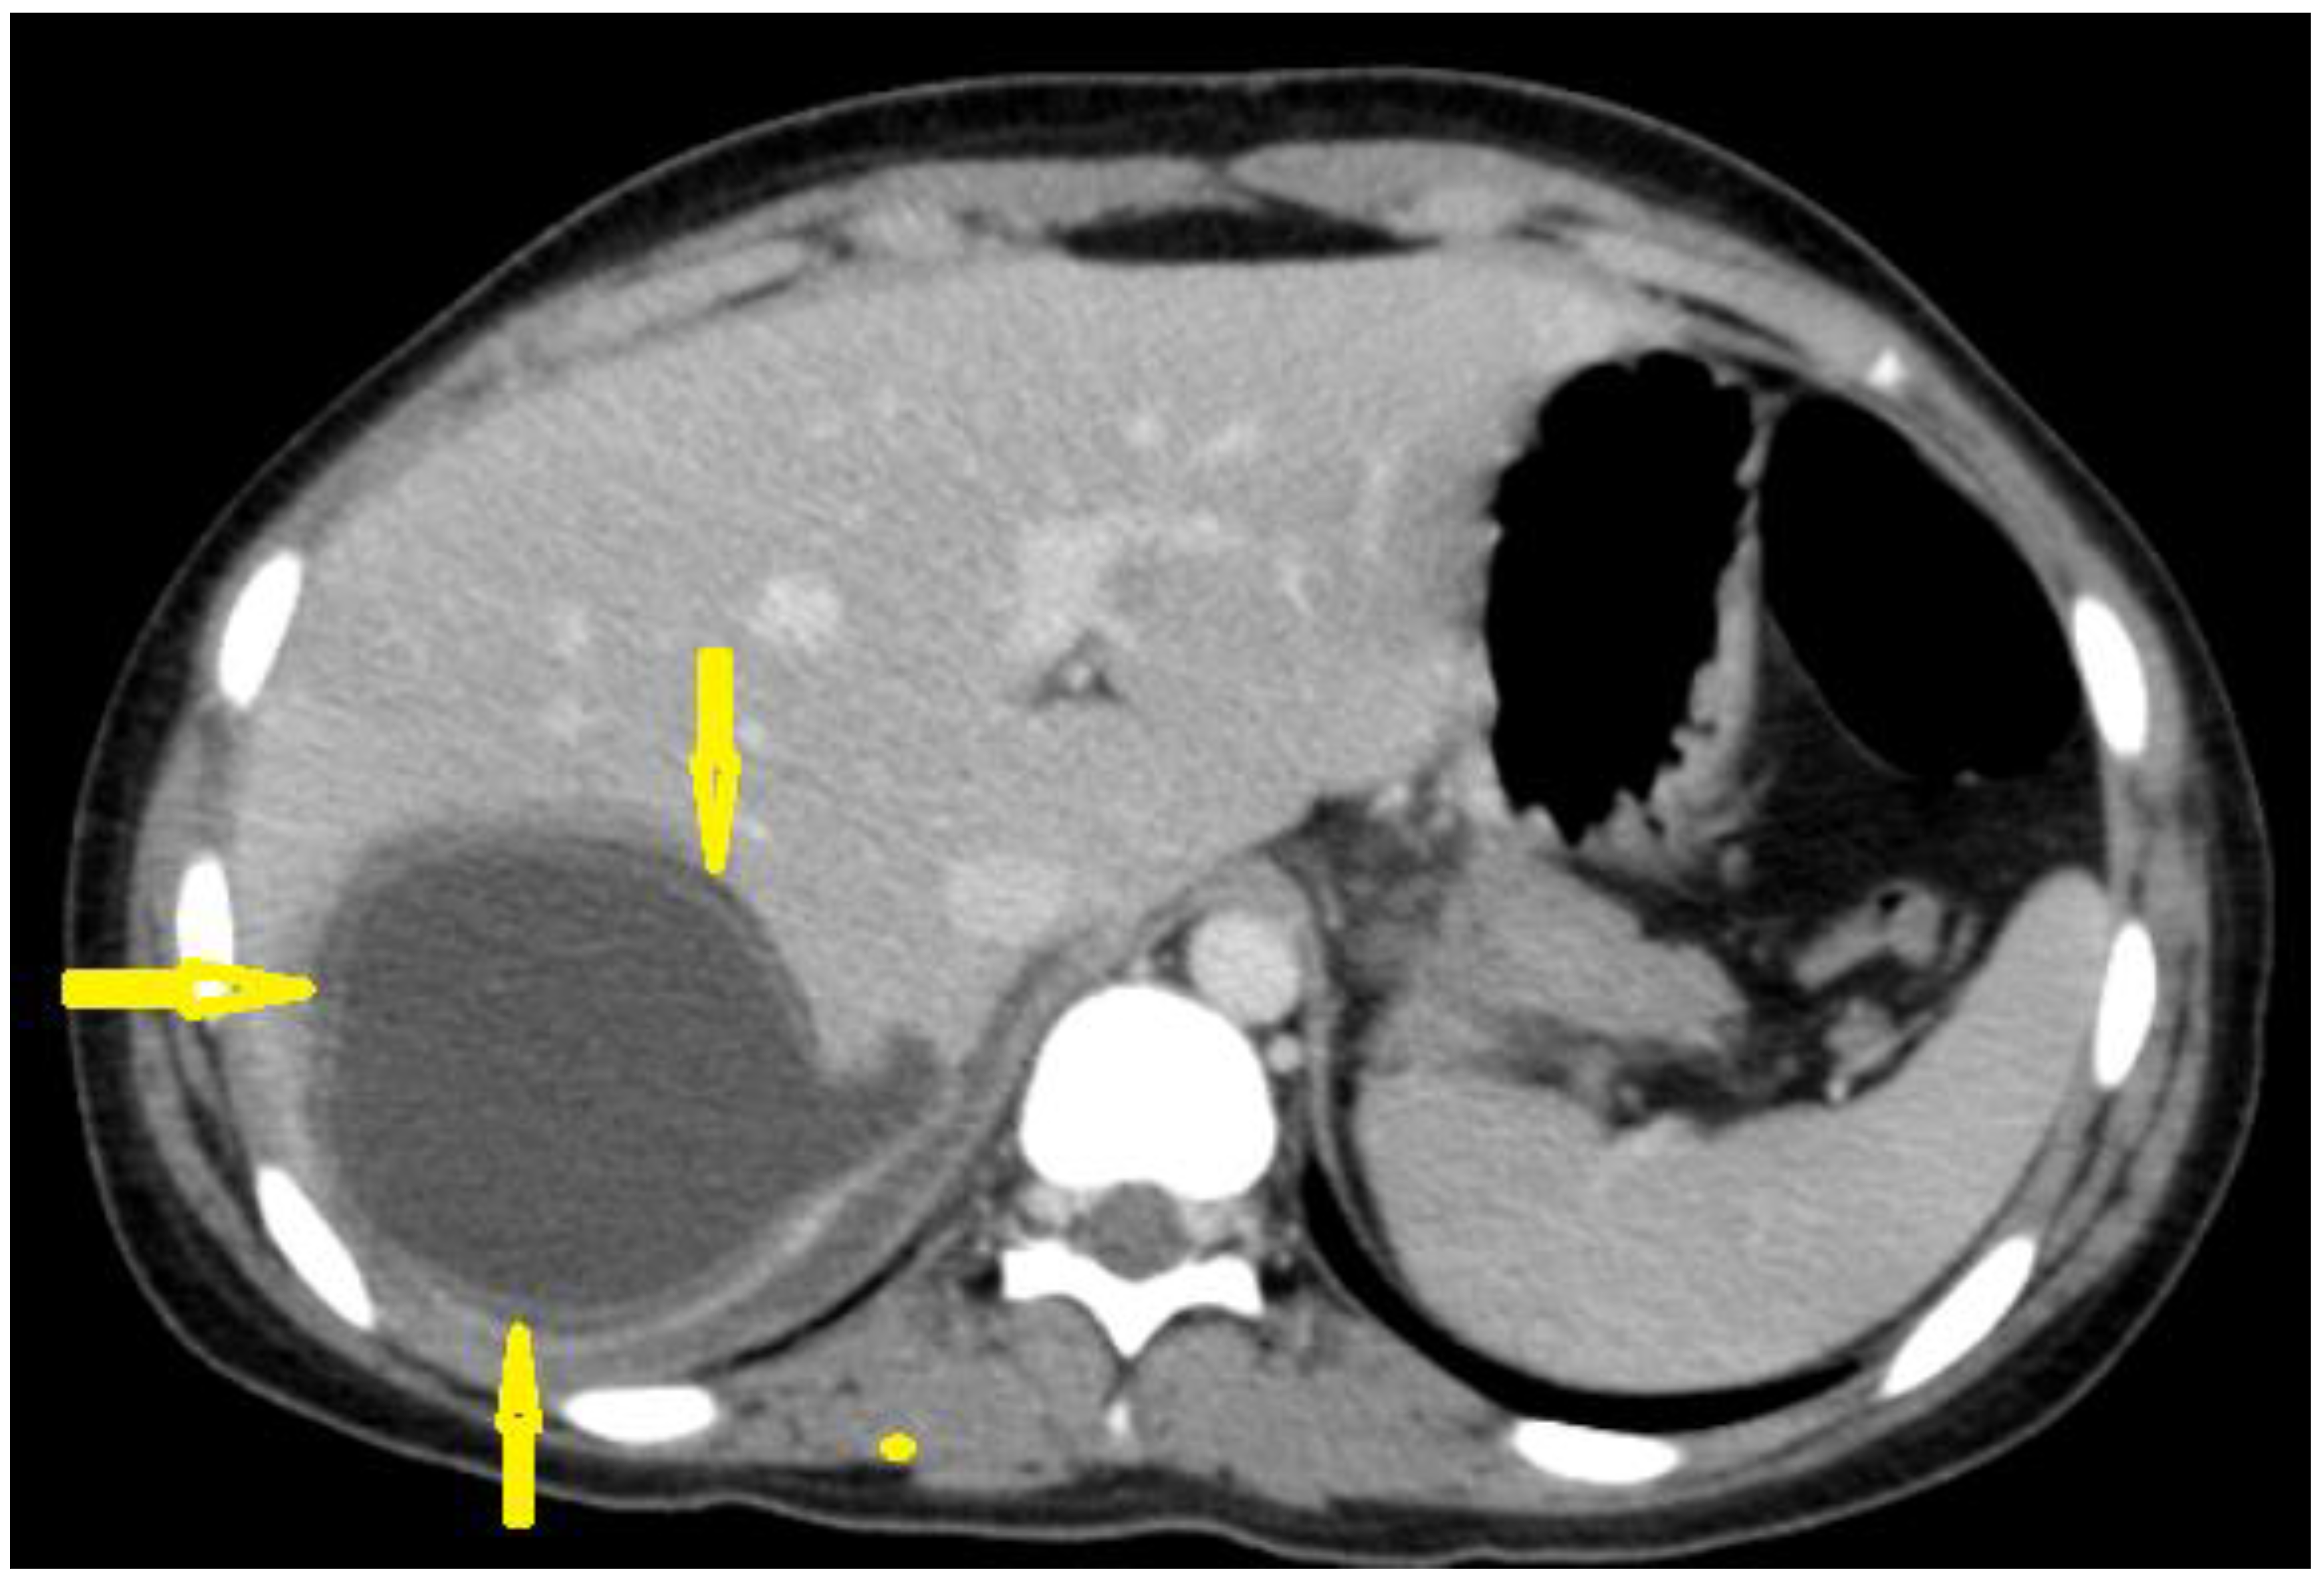

5.1. Hydatid Cysts of the Liver